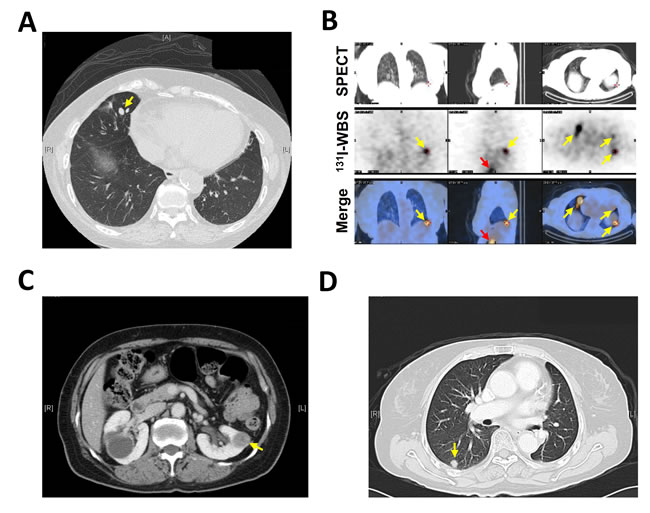

The cases #10 and #11 in G3 were the two patients with undetectable Tg. Case #10 was a 68 year-old female diagnosed with PTC without capsular or stromal invasion. After thyroidectomy, no evidence of loco-regional and distant metastasis was revealed by 131I-WBS and neck CT. The patient was enrolled in the study one year after thyroidectomy. Serum Tg of the patient was undetectable (< 0.1 ng/ml) but anti-TgAb was positive (919.1 IU/ml). However, CEC count was significantly elevated in this patient. The number of EpCAM+-CECs and TSHR+-CECs was 100 cells/ml and 152 cells/ml, respectively (Table 4). Based on these findings, CT scan (Figure 3A) and 131I-WBS with the therapeutic dose of 100 mCi (Figure 3B) were performed that ultimately confirmed the patient had multiple lung and right pelvis bone metastases.

For the case #11, the anti-TgAb was low (20.59 IU/ml) that did not contribute to the undetectable serum Tg for the patient. In accord with this notion, serum Tg was detectable (9.06 ng/ml) in another blood test when T4 treatment was interrupted. The patient had significantly elevated CEC counts with the number of EpCAM+-CECs and TSHR+-CECs equivalent of 197 cells/ml and 223 cells/ml, respectively (Table 4). The patient was subsequently revealed to have kidney and lung metastases by 131I-WBS and CT (Figure 3C and 3D). Histological proof of FVPTC was confirmed after partial left nephrectomy (image not shown). The data of these two patients with undetectable serum Tg together indicate that CEC enumeration could supplement serum Tg testing and standard imaging methods in defining metastatic status of the patients.

Figure 3: Key medical images reveal disease recurrence in cases #10 and #11. A. The image of chest CT demonstrated multiple, round but small (all less than 1 cm in diameter) pulmonary nodules (the yellow arrow indicates one of them) of case #10. These nodules were not distinguishable from the nodules derived from benign diseases such as tuberculosis. B. Single-photon emission computed tomography (SPECT, upper row) and 131I-WBS (middle low) were performed for case #10 at the 7th day after an oral dose of 100 mCi 131I. The images were superimposed (bottom row) to show the multiple focal areas of increased uptake in lung (yellow arrows) and right pelvis (red arrows). The coronal view (left panel), sagittal view (middle panel) and transverse view (right panel) of the images are shown. C. The abdominal CT image for case #11 shows a left renal middle pole tumor (2.2 x 1.7 cm) which was undistinguishable from a primary renal cell carcinoma. D. The chest CT image for case #11 shows one of the multiple small and round opacities in the lung (yellow arrow).